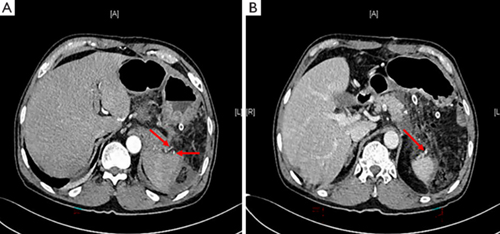

术前CT扫描和三维重建:

(A) 术前CT显示胰体尾部囊性病变(红色箭头),与脾血管毗邻关系密切;

(B)三维重建显示肿瘤与脾血管之间边界模糊(绿色箭头:脾静脉;白色箭头:脾动脉;红色箭头:胰尾病变)。